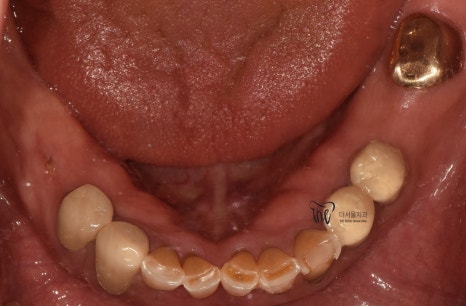

우선 교합면에서 바라보게 되면,

곳곳에 치아 결손 부위가 관찰이 되는데

이가 빠진지 시간이 꽤나 오래 되셨다는 것을

한 눈에 알아차릴 수 있습니다.

바로 결손부위를 보게 되면, 골 폭이 상당히

좁아져 있는 것을 볼 수 있는데 이는 치아 상실 후

방치 된 시간이 꽤나 오래 되었다는 것에 따른

반증이기 때문입니다.